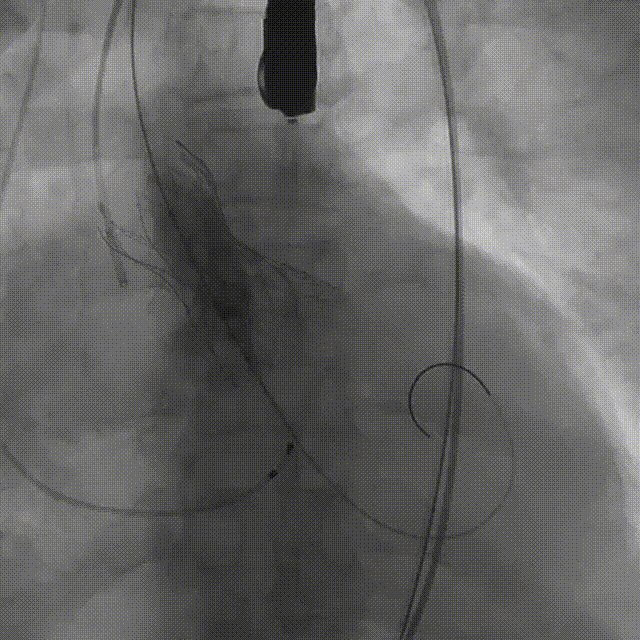

手术影像:

瓣膜开始零位定位

瓣膜逐步释放到工作位

工作位造影位置良好

瓣膜逐个脱钩

完全释放后造影,膨胀不良,有漏

25mm球囊后扩

后扩后瓣膜形态良好,造影基本无漏